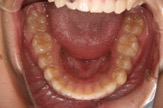

図3 初診時口腔内

図8 初診時下の歯並び